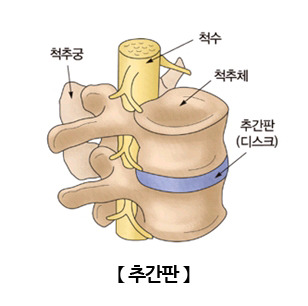

요추의 해부학적 구조는 다음과 같습니다. 우선, 요추는 제1요추에서 제5요추로 구성되어있습니다. 각 요추들 사이에는 추간판이 있으며, 요추 사이에서 발생하는 충격을 흡수하는 역할을 하고 있습니다.

추간판은 크게 외부의 섬유 조직인 섬유륜과 내부의 젤리 형태의 수핵으로 구성되고 있습니다. 이 수핵이 디스크라고 불리며, 디스크는 스프링처럼 쿠션 역활을 하면서 충격을 완화시킬 뿐만 아니라, 척추 뼈가 밀리지 않게 하고 뼈들이 서로 부딪히지 않도록 보호하게 됩니다.